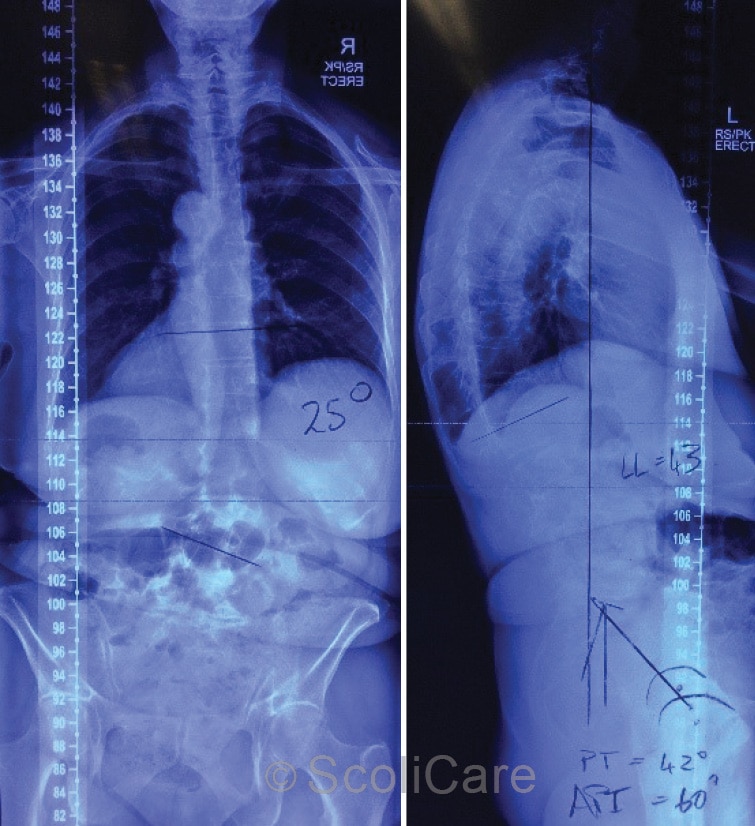

Plain films demonstrated a mild-moderate right lumbar scoliosis measuring 25° (Cobb) with an apex at L2/3 intervertebral disc (Figure 2). Extensive degenerative change in the lower lumbar spine was noted. The patient was diagnosed with progressive idiopathic scoliosis into adulthood.

Figure 2: Posteroanterior full-spine x-ray highlighting a 25° (Cobb) right lumbar scoliosis (Left),

Lateral full-spine x-ray (Right).